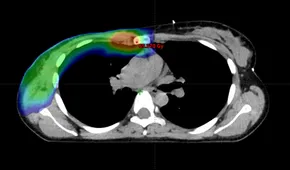

下記に商品説明や配送料・配送方法・注意事項等の説明がございます。b0b13edf-77ad-4cbe-9ee1-。お客様にとって大切な事柄を記載しておりますので、よくお読みいただき、ご了解の上ご購入をお願い致します。Breast cancer: Role of MR-guided radiation therapy。